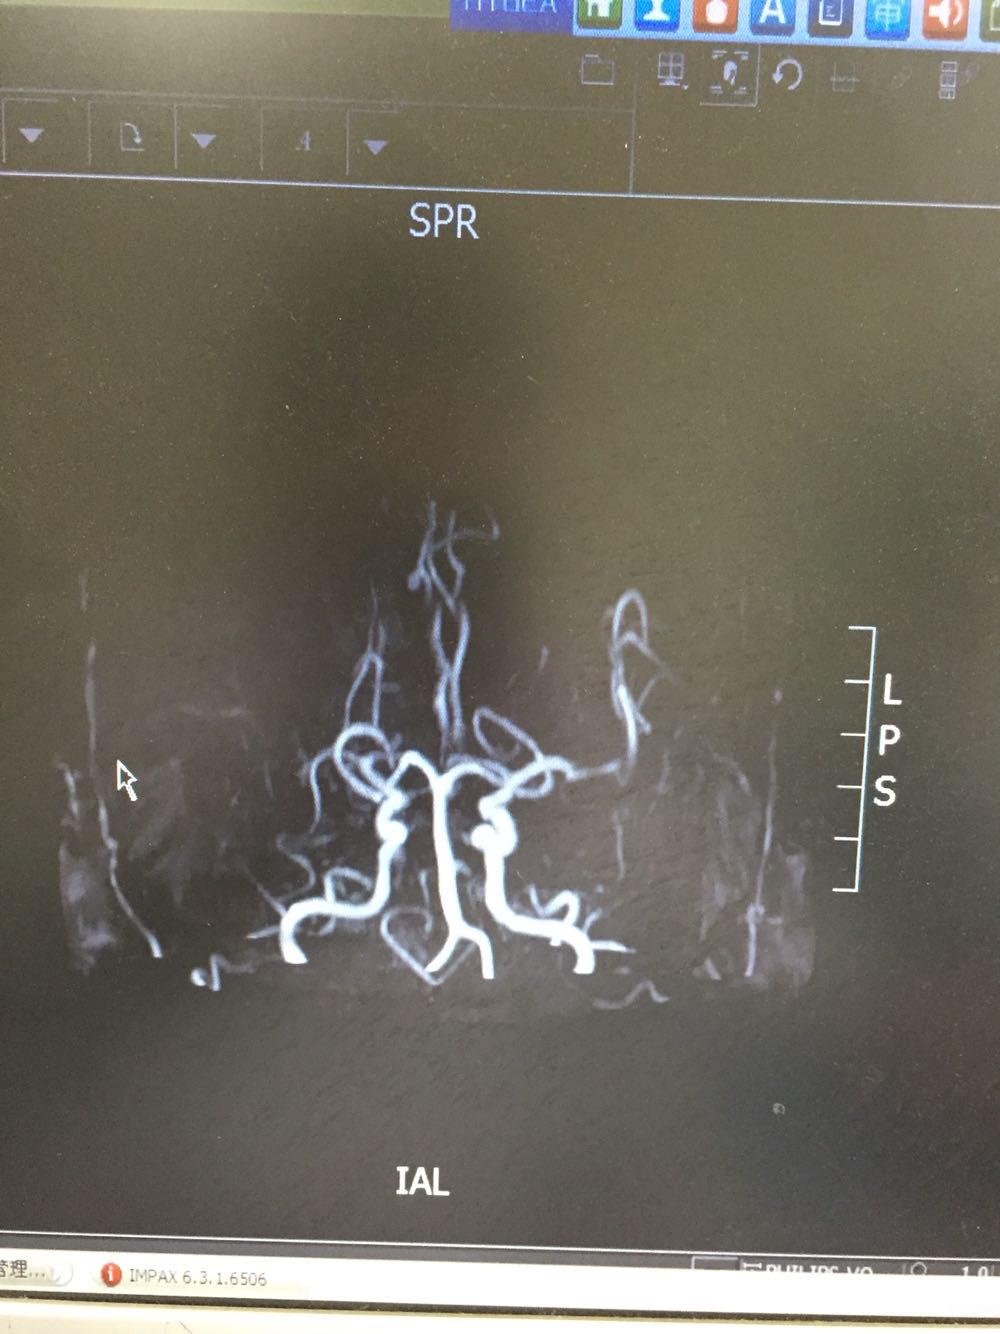

72岁男患,主因左侧肢体无力言语不能3日入院,既往否认高血压、糖尿病史 该患者于入院前三日无明显诱因出现左侧肢体无力伴言语不能,无头晕、恶心呕吐,无抽搐发作,伴有排尿障碍,于当地治疗3日无好转,为求进一步诊治来我院

血压145/92 神清,言语不能,双瞳等大同圆,伸舌居中,左侧肢体肌力0级,右侧肢体肌力4级 双下肢病理症未引出 颈强阴性

患者急性右侧大脑中动脉闭塞导致大面积脑梗死。遗留左侧肢体瘫痪可能性大。目前一般状态尚可